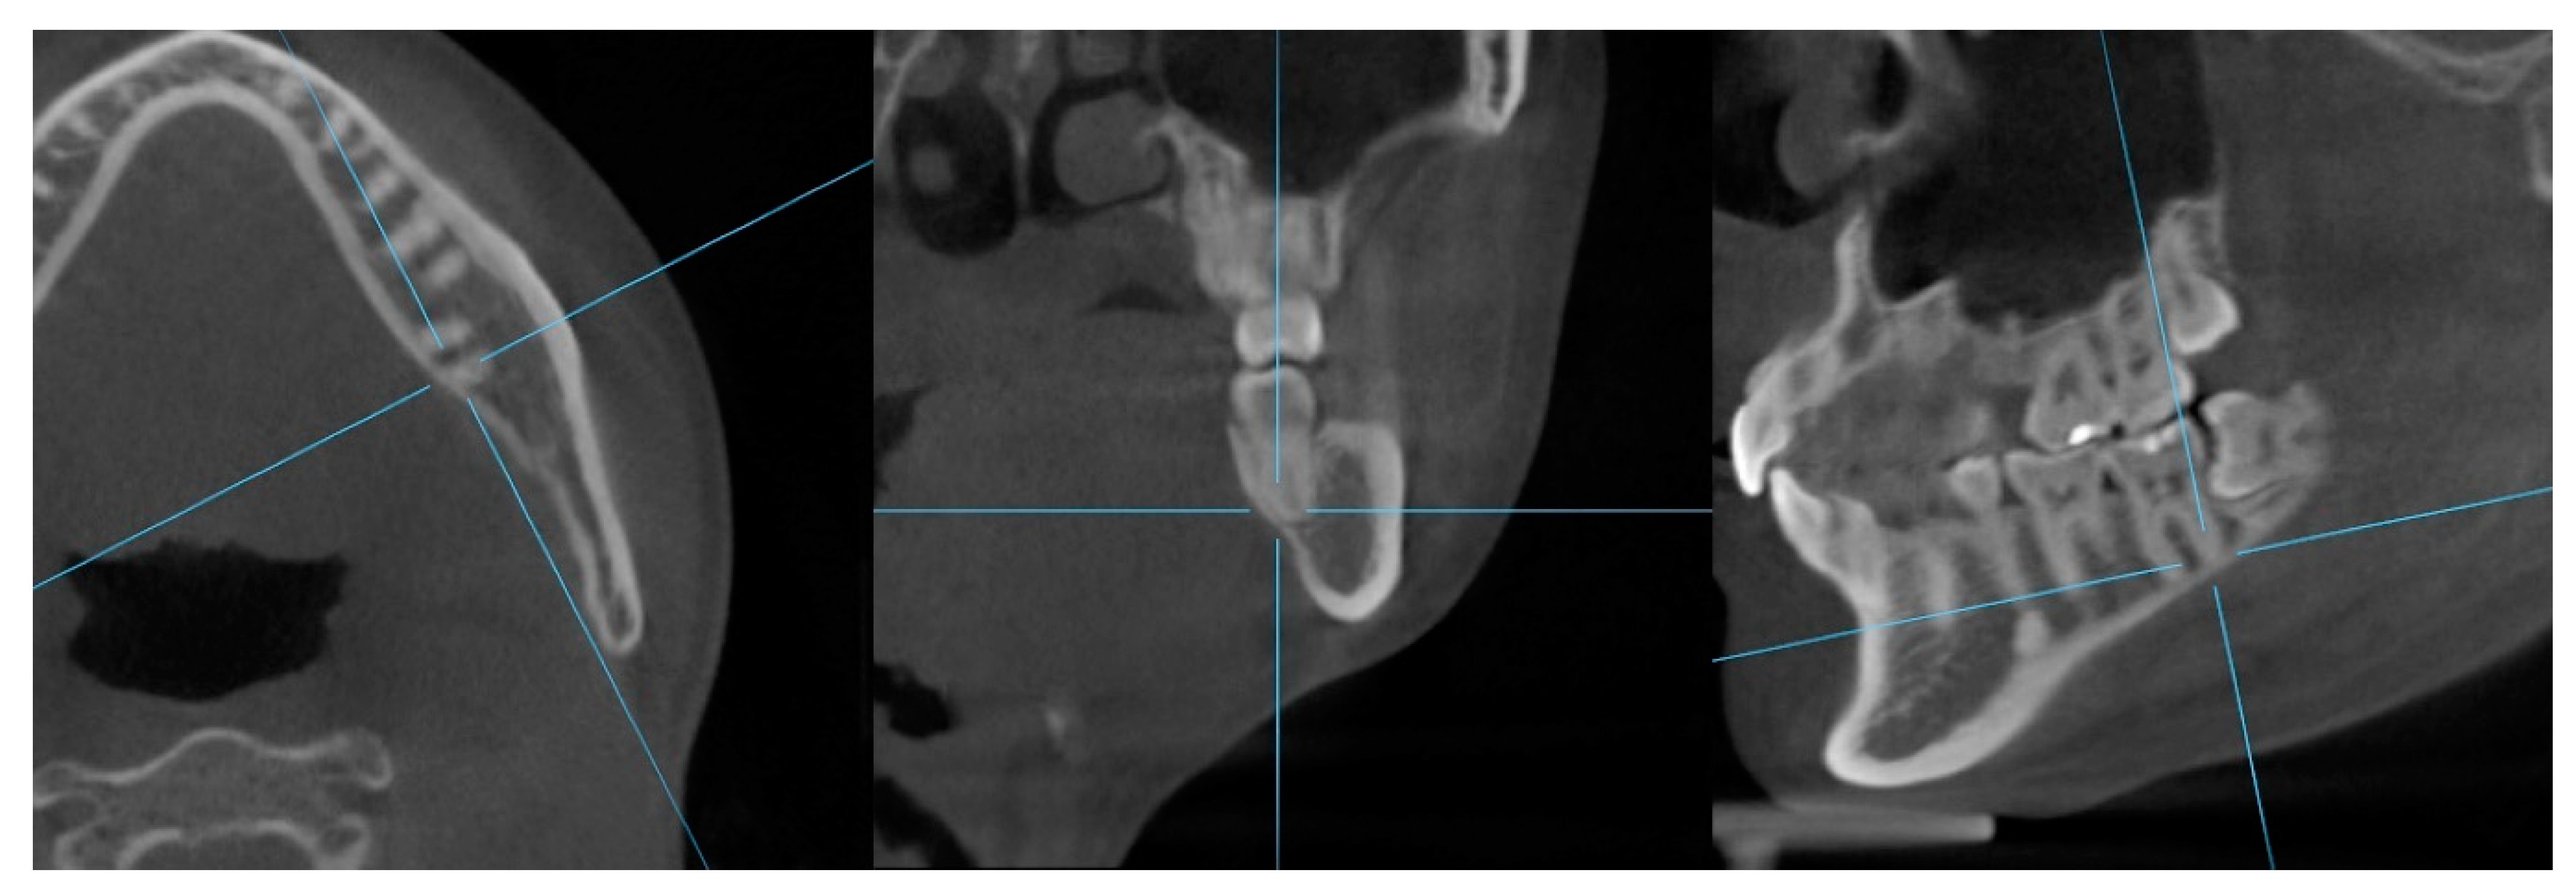

Additionally, contact between the first and second molar roots and lingual cortical bone was assessed. If contact between molar roots and lingual cortical bone in the horizontal plane was suspected, the contact was confirmed in multiplanar reconstruction images (Figure 4).

Figure 4.

Confirmation of contact between mandibular molar roots and lingual cortical bone with multiplanar reconstruction images.